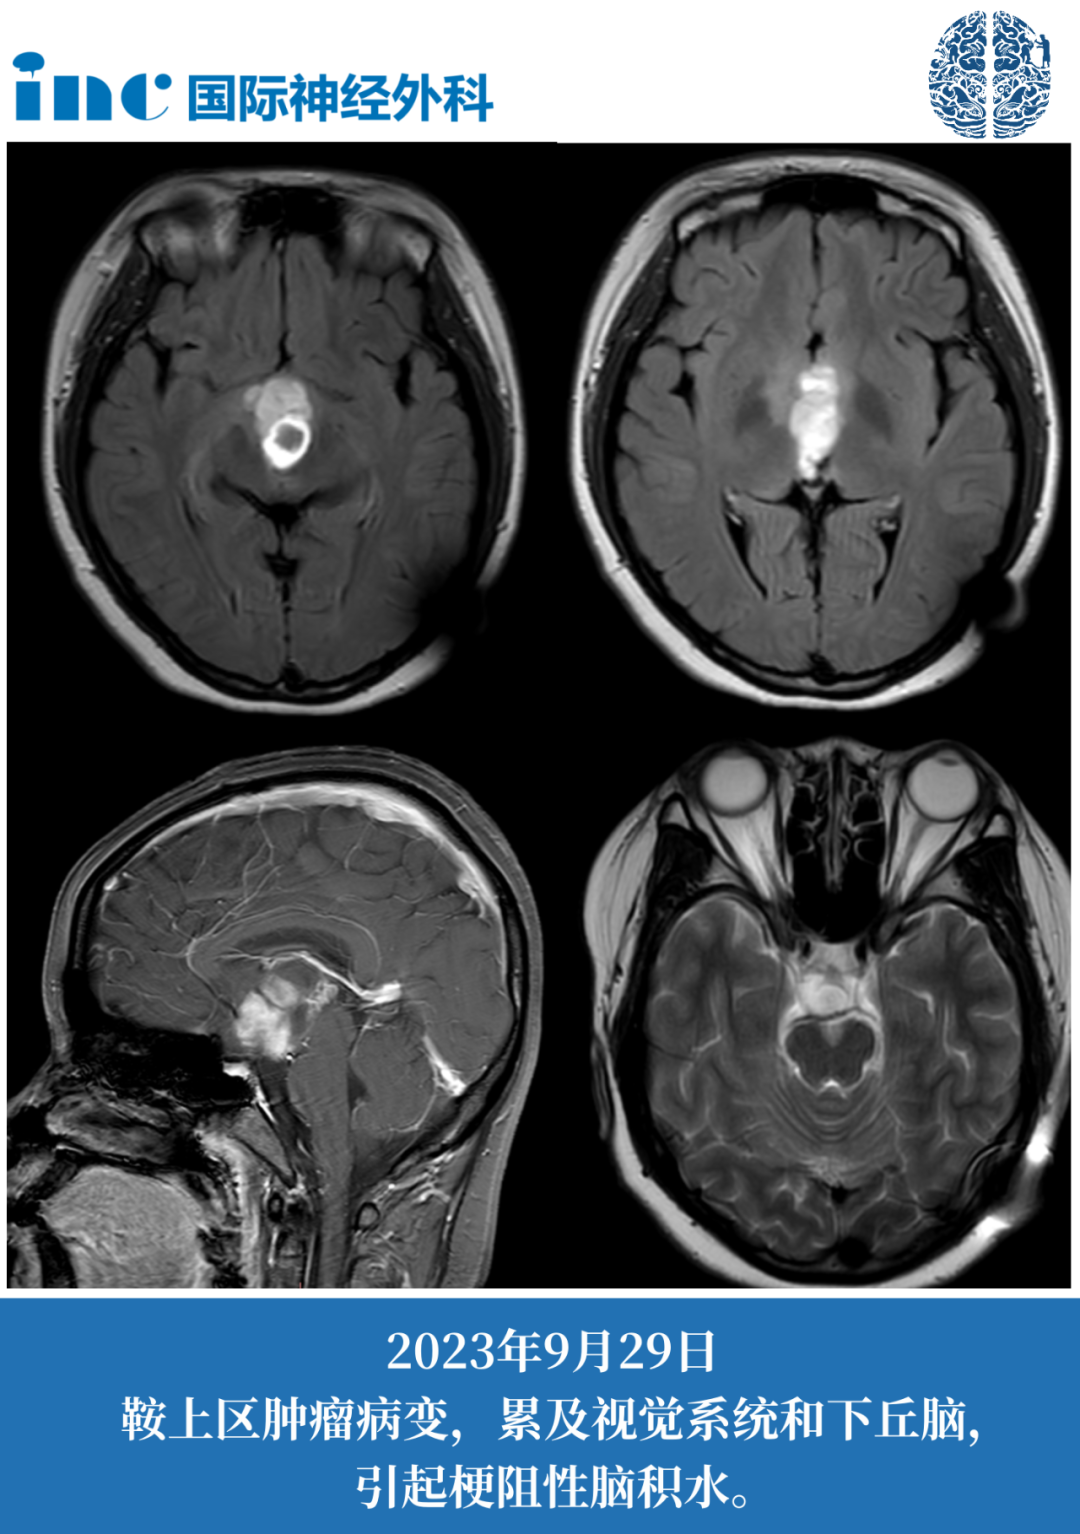

患者信息:14岁女孩,7年鞍区肿瘤病史、头晕、头痛、体重增加快、早熟。既往脑室腹腔分流术。

复查发现肿瘤有很明显的占位效应,危及视神经及视交叉(两者已经被肿瘤累及),有明确的手术指征。